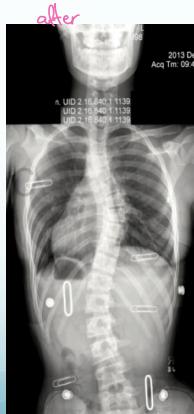

Surgical Treatment

Indications:

- Curves >40° in skeletally immature patients

- Progressive curves

Procedure:

- Correction

- Instrumentation

- Fusion

Surgery

- Adult documented progressive curves